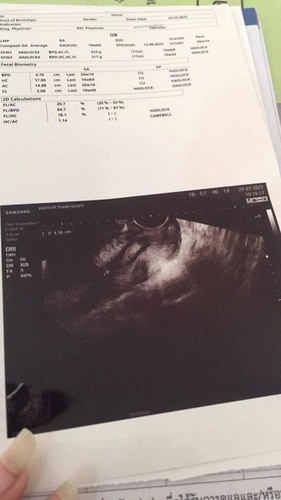

แม่รู้เพศกันหรือยังคะ วันนี้ไปซาวด์มาหมอบอกไม่บอกเพศงงเลย พอจะดูออกไหมคะ 19สัปดาห์5วัน